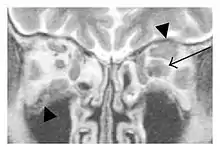

![]() Swelling of the left superior and lateral rectus muscles, a mass lesion around the left optic disc (arrow), and enlargements of the left supraorbital nerve and the right infraorbital nerve (arrow heads) in a 60-year-old man with a serum IgG4 of 463 mg/dL.[1] (T1-weighted MRI) |